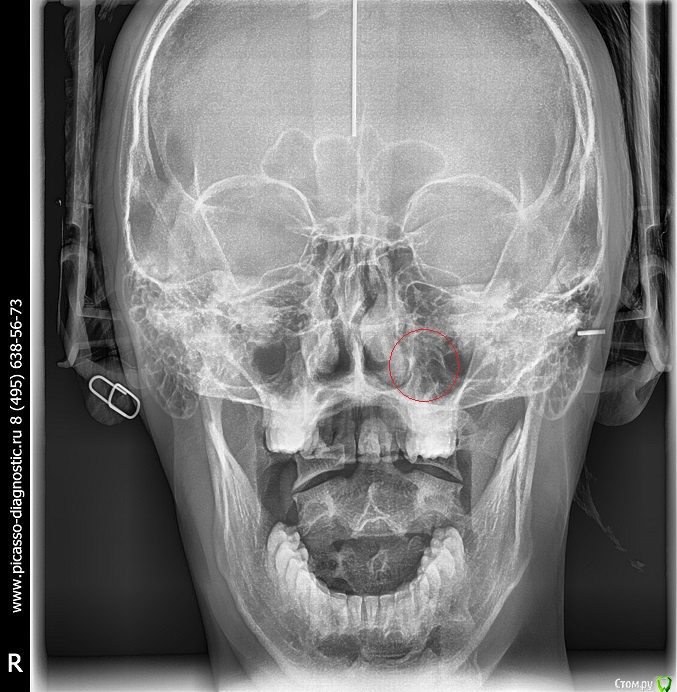

Arseny0111 Опубликовано 27 сентября, 2015 Поделиться Опубликовано 27 сентября, 2015 (изменено) Здравствуйте,в ходе драки получил удар,в верхнюю челюсть,сразу же не значительно сменился прикус и искривилась носовая перегородка.Есть ли на снимках отклонения от нормы?трещина?и т.д.Что с этим делать к кому обращаться?Из исследований дополнительно имеется МСКТ(3D)Спасибо. Изменено 27 сентября, 2015 пользователем Arseny0111 Ссылка на комментарий

Arseny0111 Опубликовано 1 октября, 2015 Автор Поделиться Опубликовано 1 октября, 2015 Здравствуйте,в ходе драки получил удар,в верхнюю челюсть,сразу же не значительно сменился прикус и искривилась носовая перегородка.Есть ли на снимках отклонения от нормы?трещина?и т.д.Что с этим делать к кому обращаться?Из исследований дополнительно имеется МСКТ(3D)Спасибо.Уважаемые доктора,помогите пожалуйста.Неужели нет компетентных специалистов в этой области? Ссылка на комментарий